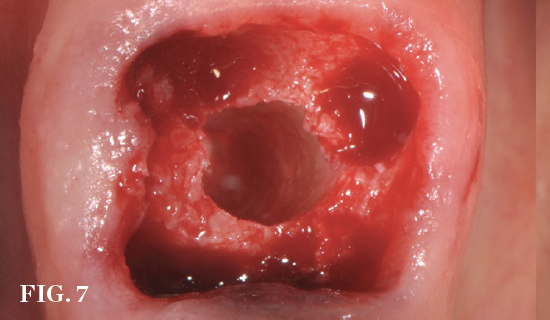

(7.) Restoratively centered guided osteotomy and implant insertion.

Figure 7